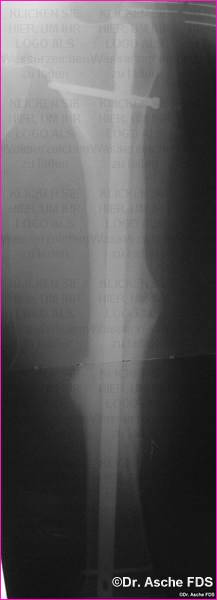

Die unten beschriebene Art der Valgisierung- und Drehosteotomie

wurde vorgenommen.

Die Stabilisierung erfolget mit einem Kompressionsnagel

T2

Nach 3 Monaten war die Fraktur fest verheilt, der Patient

konnte beschwerdefrei laufen

Drehung und Achse waren Korrekt. Auch bei Drehfehlern

von 10° sollte immer wieder die Frage einer Korrektur erwogen werden.